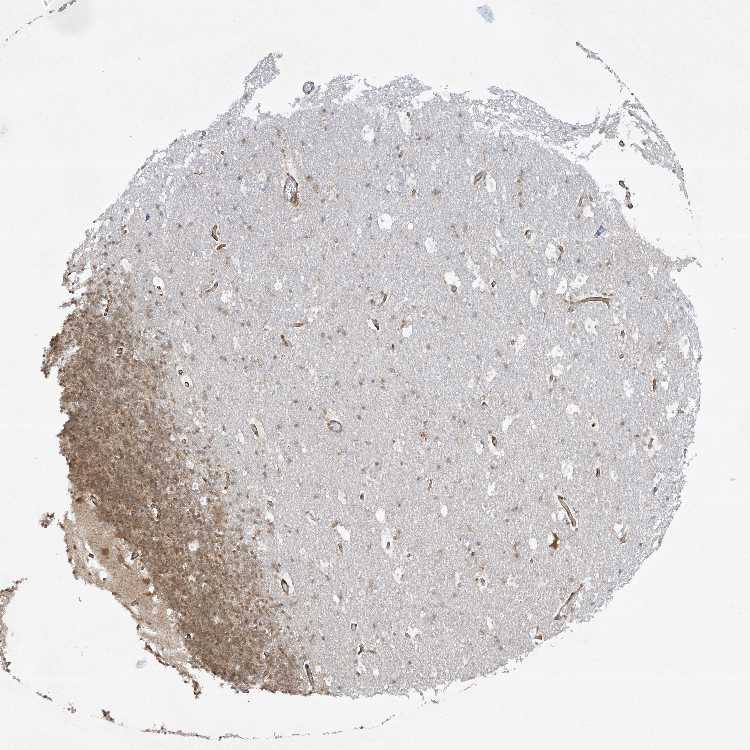

CEREBELLUM - Antibody stainingi

Antibody staining in the annotated cell types in the current human tissue is reported as not detected, low, medium, or high, based on conventional immunohistochemistry profiling in selected tissues. This score is based on the combination of the staining intensity and fraction of stained cells.

Each image is clickable and will lead to virtual microscopy that enables deeper exploration of all samples and also displays staining intensity scores, fraction scores and subcellular localization as well as patient and tissue information for each sample.

Antibody HPA035645Antibody HPA042608

Purkinje cells MediumLow

Cells in granular layer MediumNot detected

Cells in molecular layer Not detectedNot detected